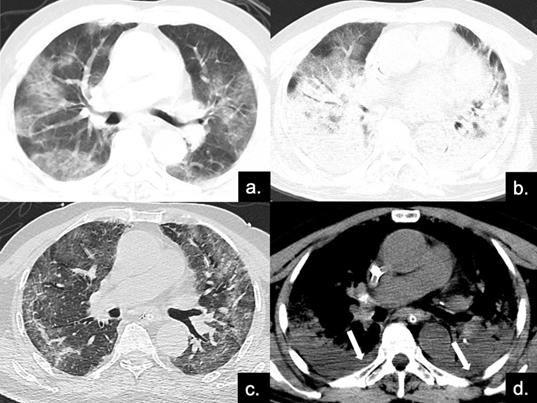

Figure 4

Series CT scans in an 85-year-old man with COVID-19 pneumonia in the severe group. (a) Scan obtained on disease day 4, showing patchy ground-glass opacities plus interlobular septal thickening (crazy paving). The Predominant CT pattern was of GGO type, with 12 as total CT score. (b, d) Scan obtained on day 10, the disease progressed rapidly to ARDS (PaO2 / FiO2 continued to decrease with a minimum of 85), and the patient was treated with ECMO. Figure b is the lung window, showing diffuse distribution of consolidation and bronchial meteorology in both lungs, mainly dorsal, while the crazy paving can also be seen on the ventral side. Figure d depicts the soft tissue window, and pleural effusion can be found under the dorsal pleura (red arrows). The predominant CT pattern was of consolidation type, with 25 as total CT score. (c) Scan obtained on day 40, lung lesions were further absorbed and reticular involvement was increased, accompanied by fibrotic changes. The predominantly CT sign was the reticular pattern, with 17 as total CT score.